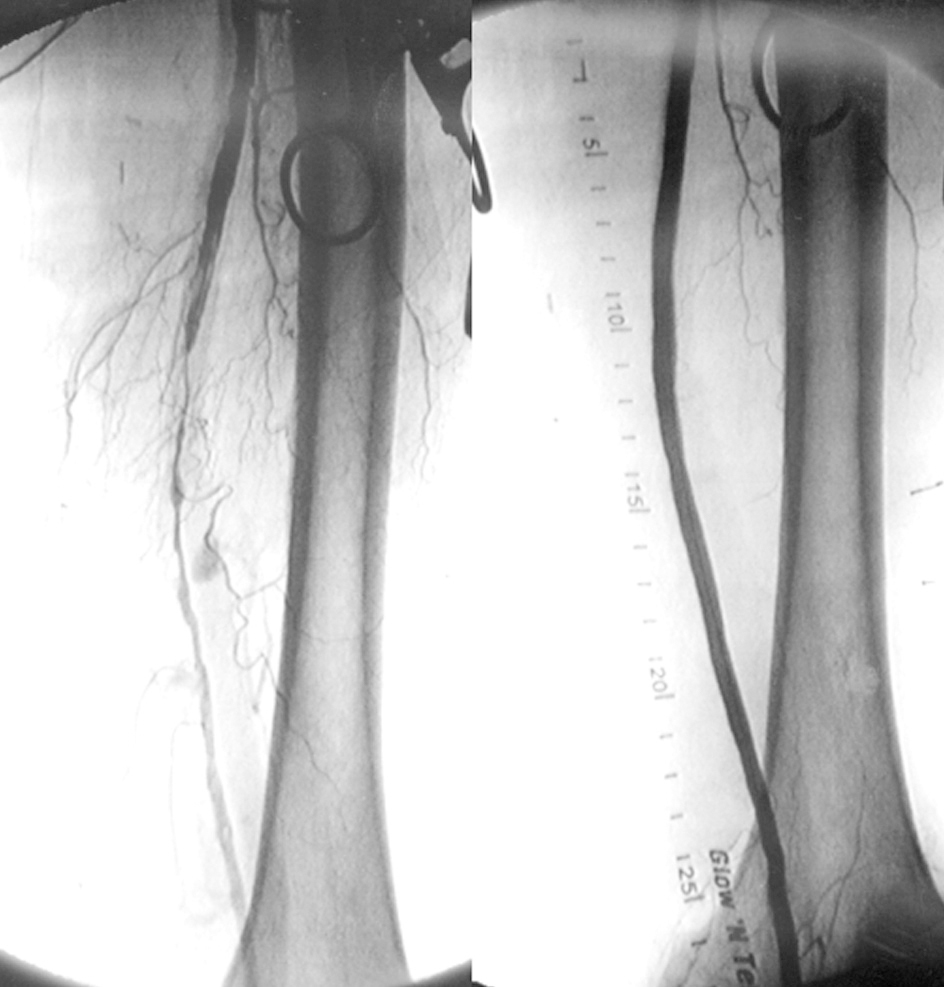

El manejo quirúrgico puede ser cirugía endovascular con excelentes resultados, y la cirugía abierta convencional, ambos dependerán de la evaluación de cada caso.

- Angioplastias periféricas a cualquier nivel, excepto corazón y cerebral.

- Bypass arterial y venoso a cualquier nivel, excepto cerebral